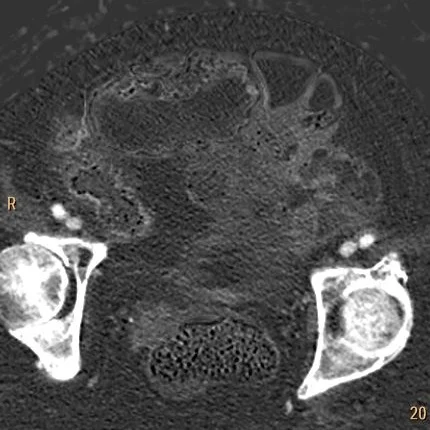

Iodine map: There is perfusion!

Iodine overlay: Nicely depicts perfusion to these loops. We could have treated this conservatively.